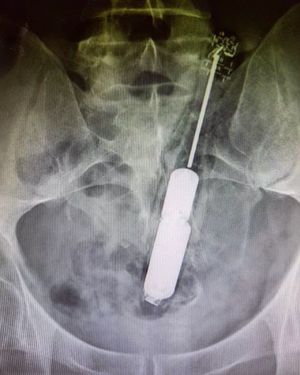

Don’t forget your toothbrush!!! Out of all the weird items that can be inserted into the anus, this is undoubtedly a very questionable one - a toothbrush!The patient presented to the ER after attempts at self-removal failed all at once. Dentally related rectal foreign bodies are very rare and there are many reasons given for their presence in the rectum, most commonly accidental insertion, assault, and psychosexual motives.These type of cases pose a challenging diagnostic and therapeutic dilemma due to the fact that retained rectal foreign bodies may present with perforation, obstruction, or bleeding; necessitating fast intervention. The toothbrush was surgically recovered from the rectosigmoid junction using biopsy forceps.